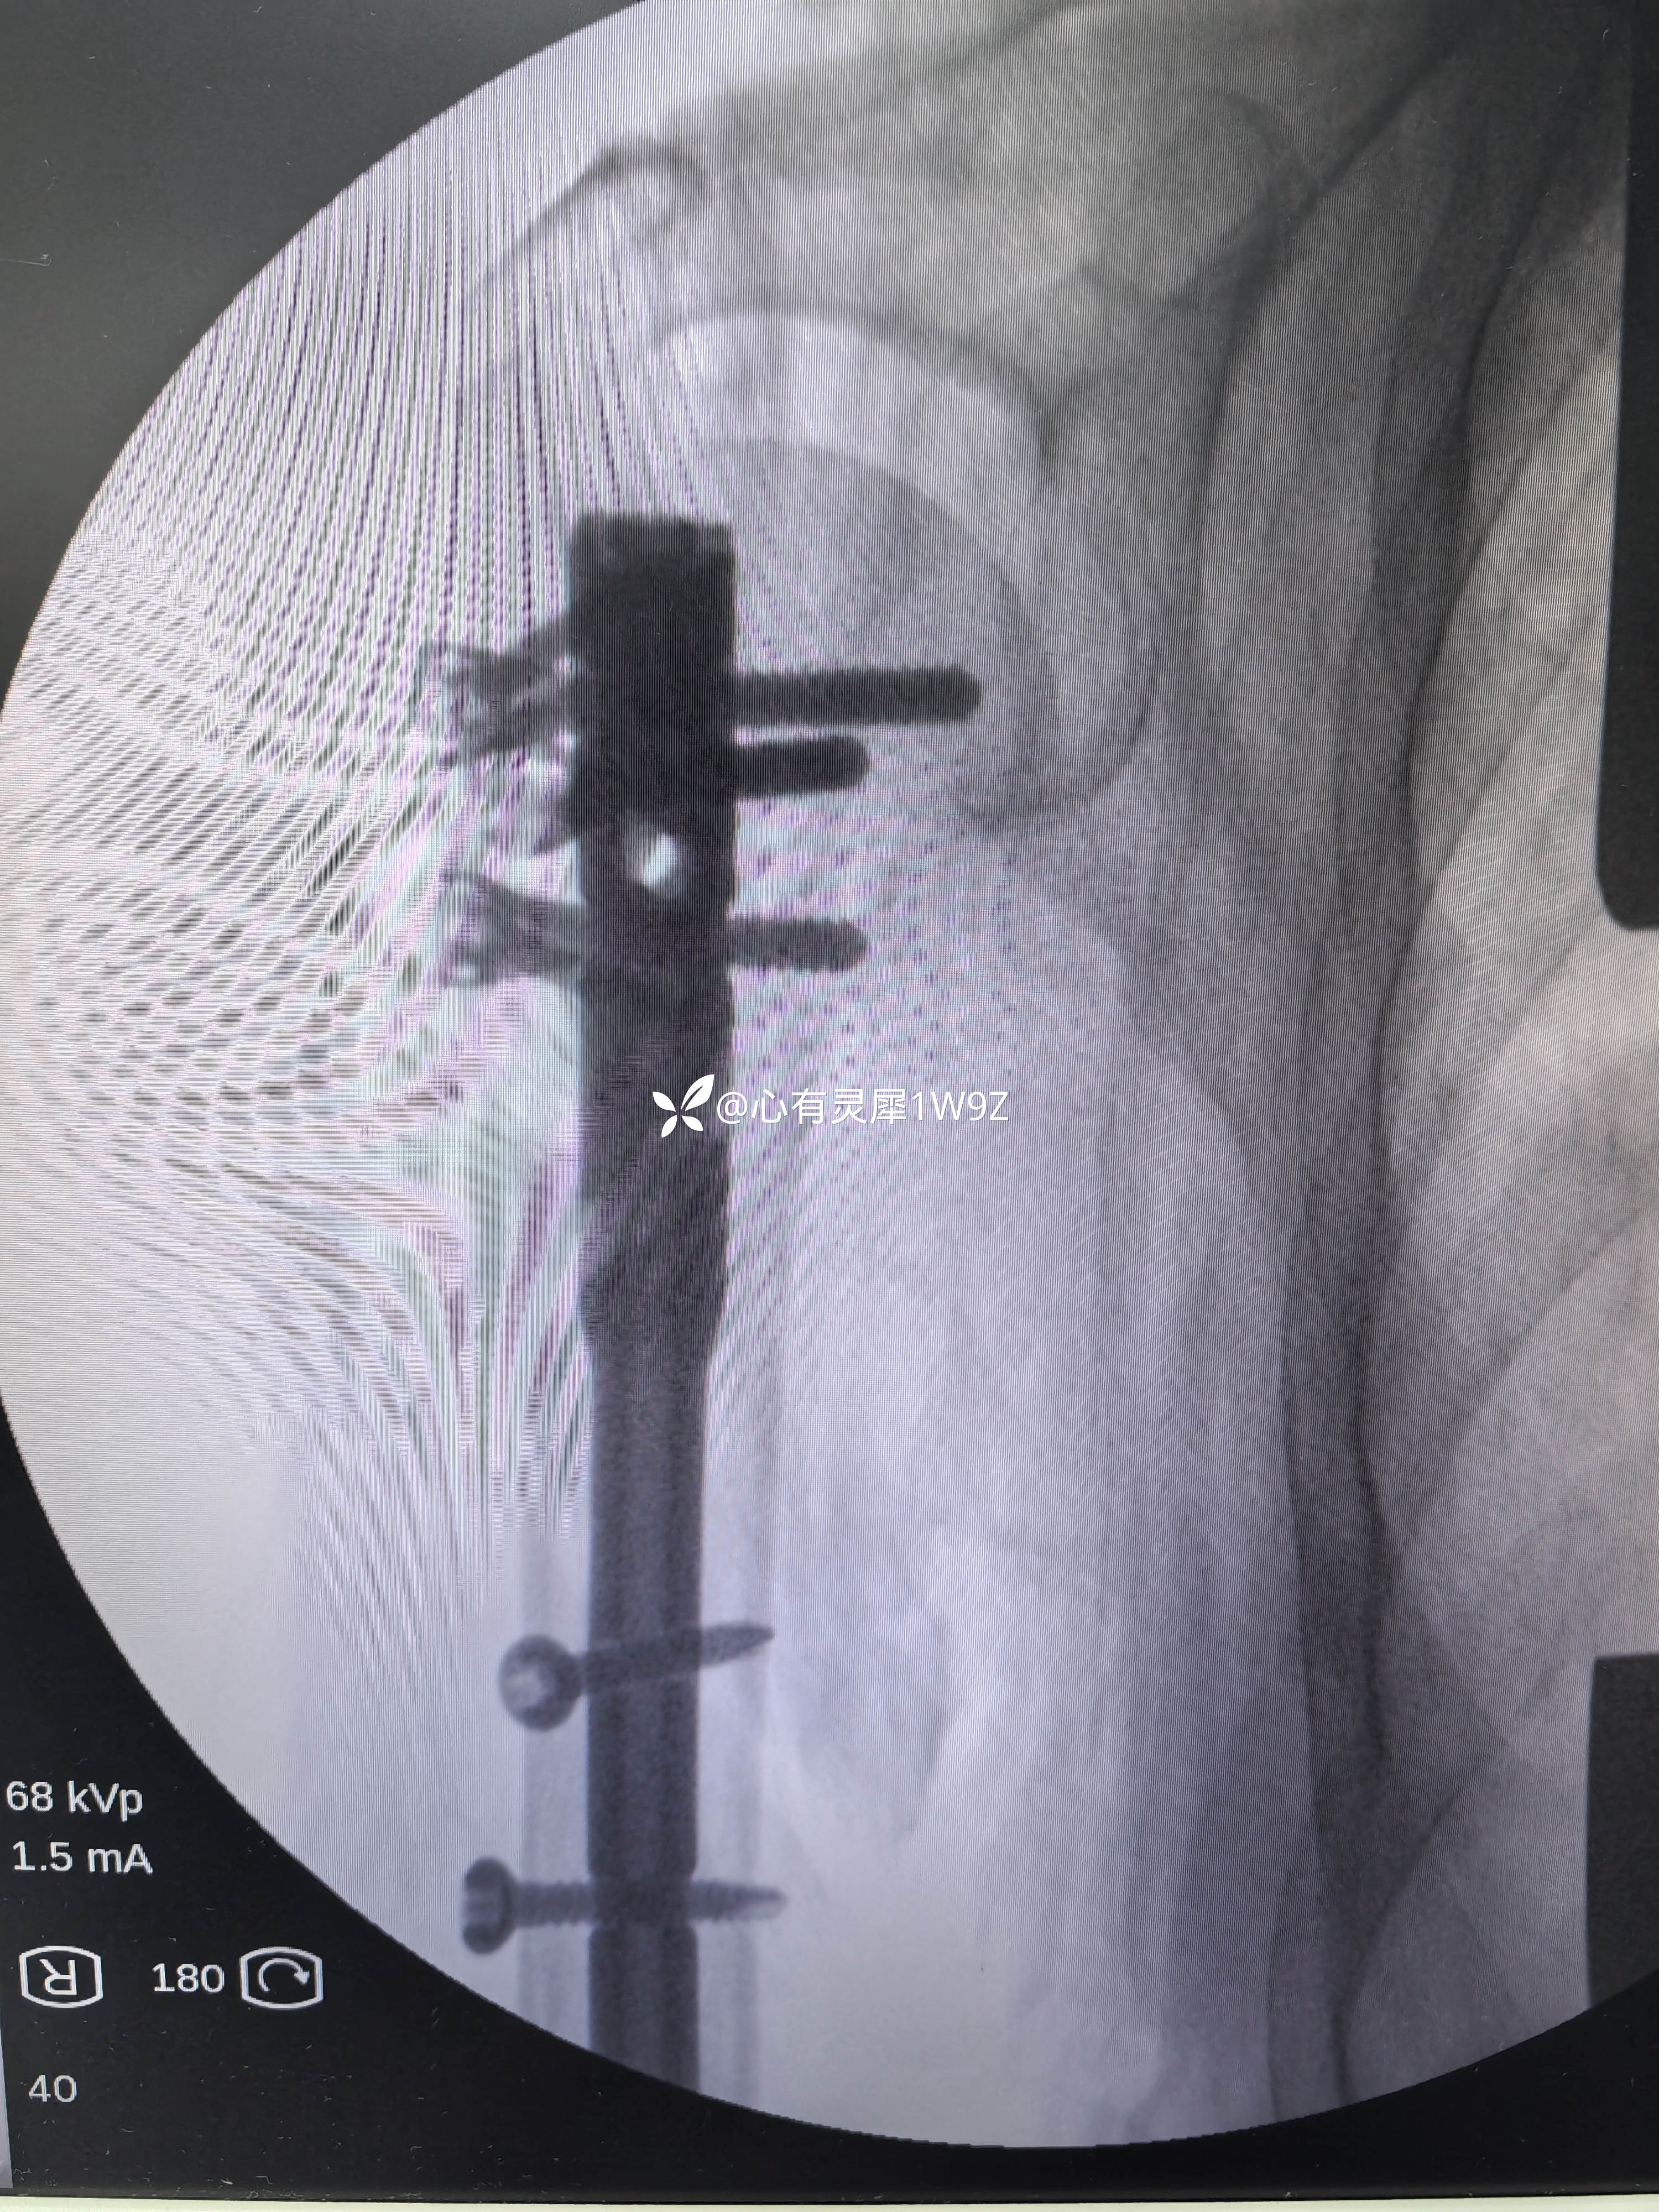

高龄肱骨外科颈骨折(陈旧性?)髓内钉固定

【临床诊断】:右侧肱骨外科颈骨折

【治疗经过及结果】:患者高龄严重骨质疏松,考虑到肱骨近端比较完整,骨折移位较大,时间较长,术中复位困难等因素。给予全麻下切开复位髓内钉固定。术中骨折断端肉芽组织较多,复位困难,断端皮质很薄,清理断端肉芽组织,新鲜化断端,复位后选择较粗髓内钉固定。术中见骨折固定稳定,将髓内钉开口环钻取的松质骨混合异体松质骨植于断端。

肱骨近端髓内钉对于严重骨质疏松的外科颈骨折具有增加稳定性的优势,尤其是近端锁钉的钉中钉设计很巧妙,但是操作复杂,手术时间较长。